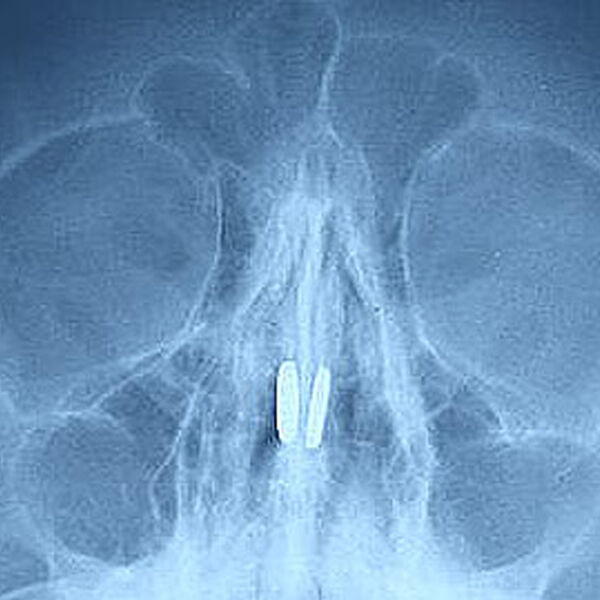

В Нижегородской области врачи извлекли из носа ребенка магнитные шарики, которые притянулись друг к другу. Об этом в Telegram-канале сообщил главный редактор местного издания «Стационар-Пресс» Алексей Никонов.

Маленький пациент был доставлен в медицинское учреждение с жалобами на боль в носу и проблемы с дыханием. В ходе обследования в носовых пазухах были обнаружены магниты от игрушки, которые притянулись друг к другу через носовую перегородку.

Инородные тела извлекли специальным крючком, серьезных повреждений мальчик не получил.